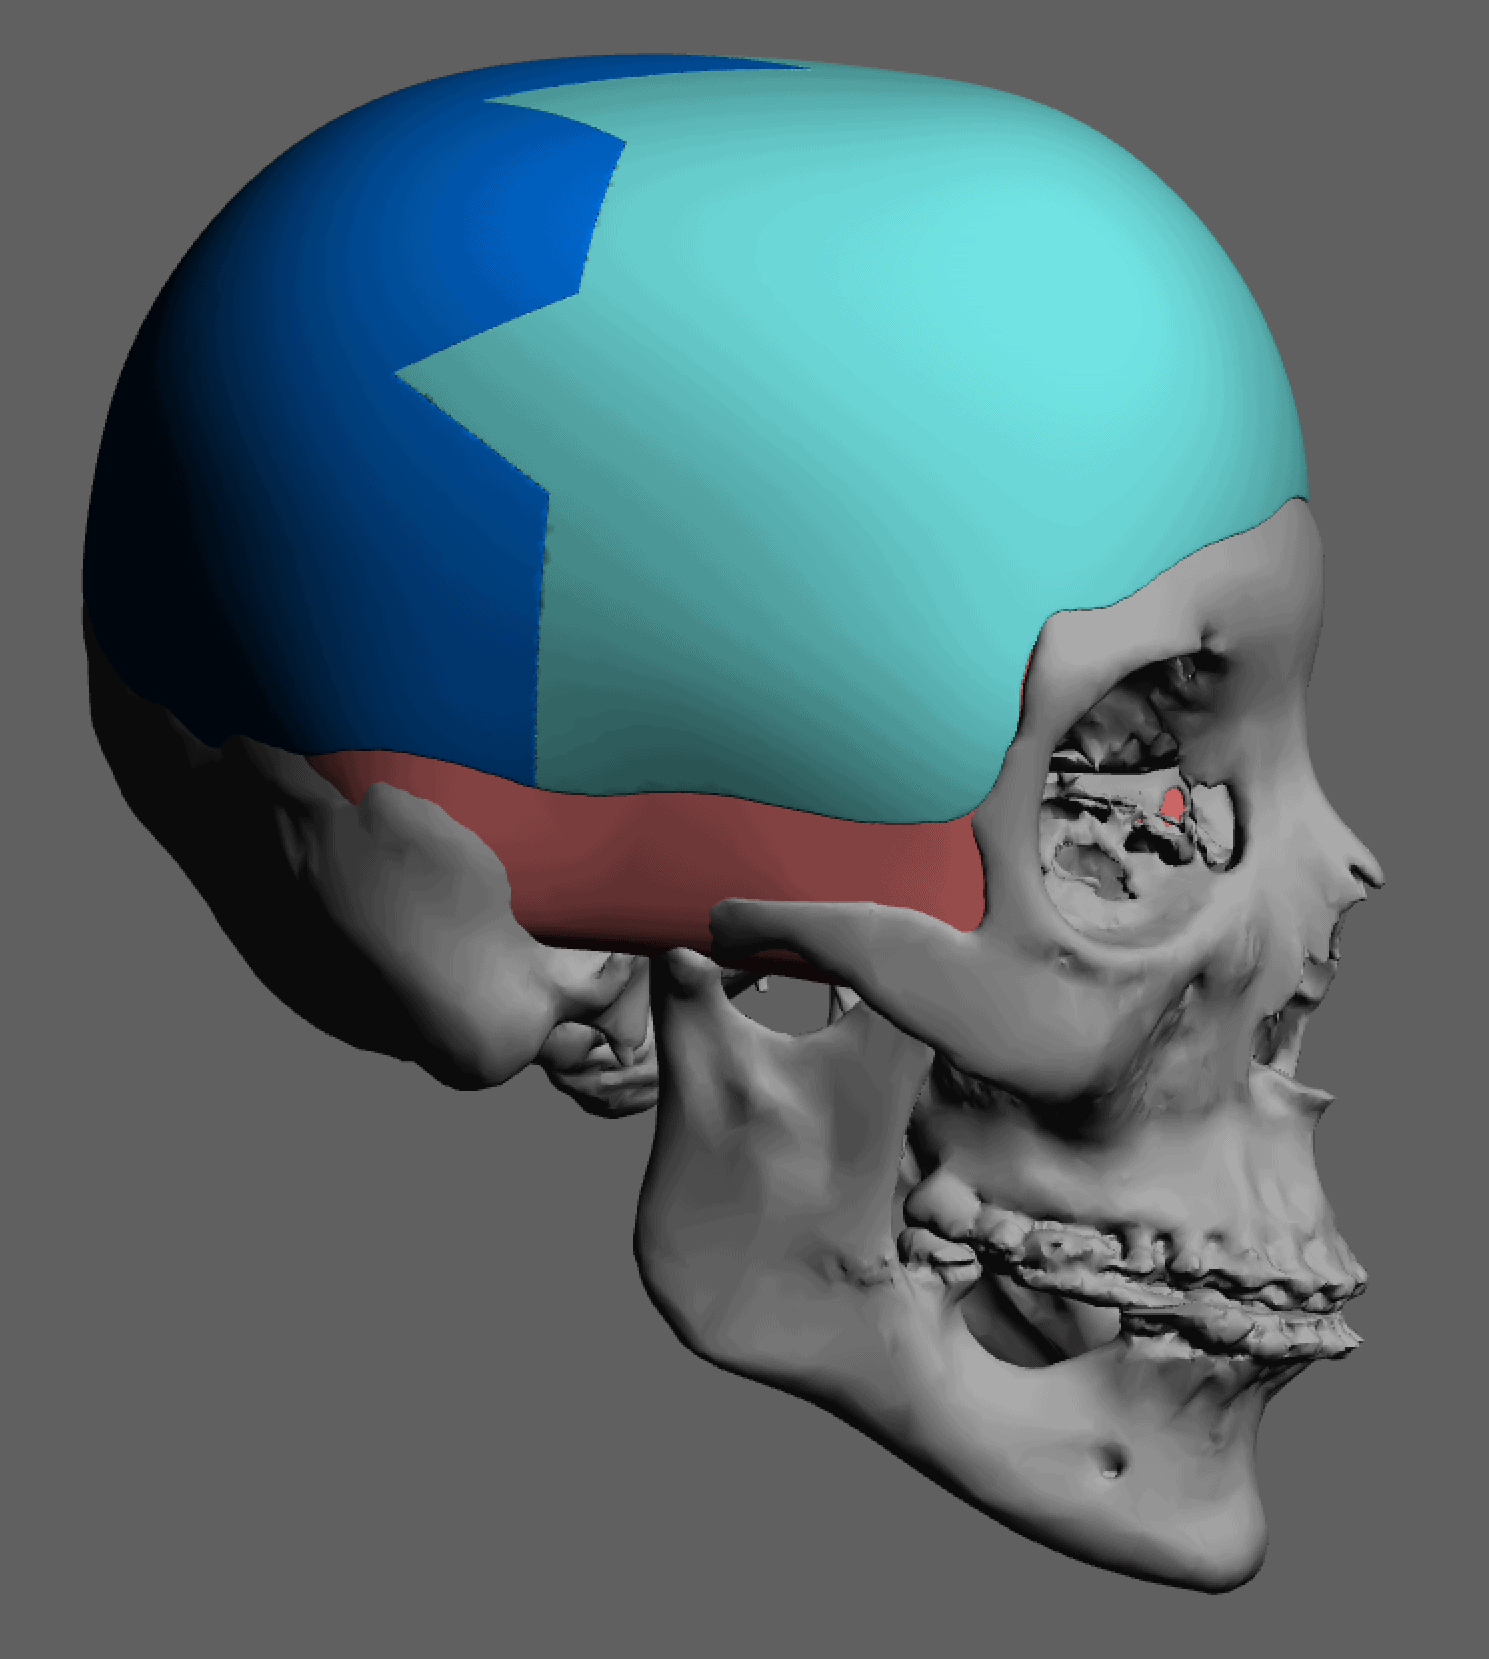

Patient 84

Desire for change of head shape from front view form an inverted V shape to a rounder and wider head shape.

Placement of custom extended forehead-temporal implants through incisions in the crease behind the ear. (he had a prior back of head skull implant which is green in the implant designs and which the head widening implants partially covered it)

Desire for change of head shape from front view form an inverted V shape to a rounder and wider head shape.

Placement of custom extended forehead-temporal implants through incisions in the crease behind the ear. (he had a prior back of head skull implant which is green in the implant designs and which the head widening implants partially covered it)